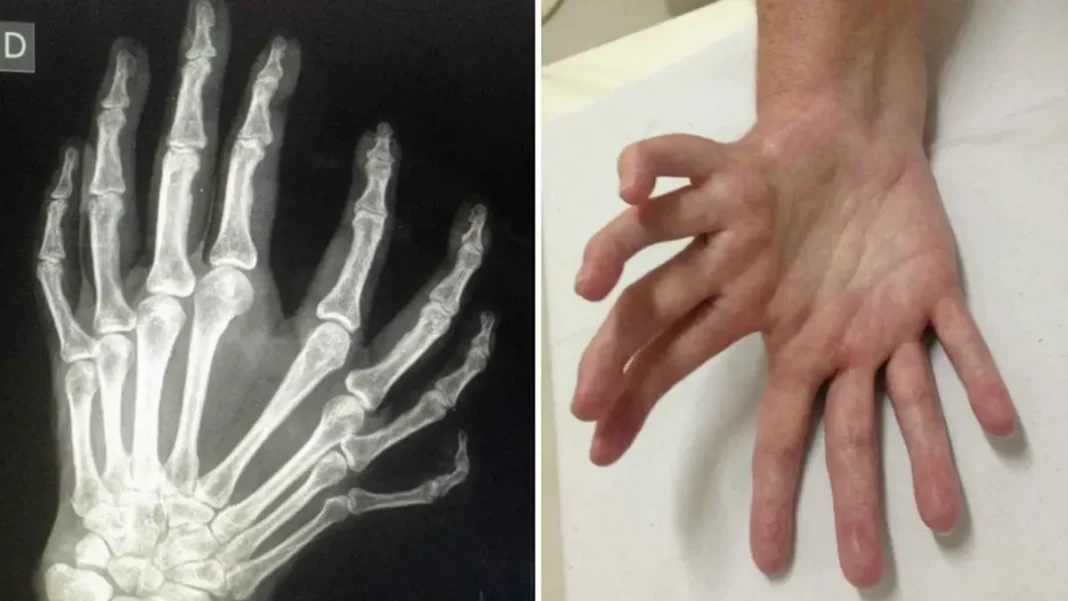

The medical fraternity has been astounded by Aisha’s mirrored hand. Specialists in various fields, including dermatology, orthopedics, and genetics, have examined her extensively, attempting to understand the underlying cause behind this unique occurrence. Thus far, they have been unable to find any documented cases similar to Aisha’s condition, making her case a true medical anomaly.

While the precise reason for Aisha’s mirrored hand remains unknown, experts have put forward several theories to explain this extraordinary phenomenon. One hypothesis suggests that it could be a result of a rare genetic mutation, altering the growth patterns and pigmentation of her skin cells. Another theory revolves around a potential environmental factor, such as exposure to a specific substance or element during her early development. However, more research and analysis are required to validate these hypotheses.